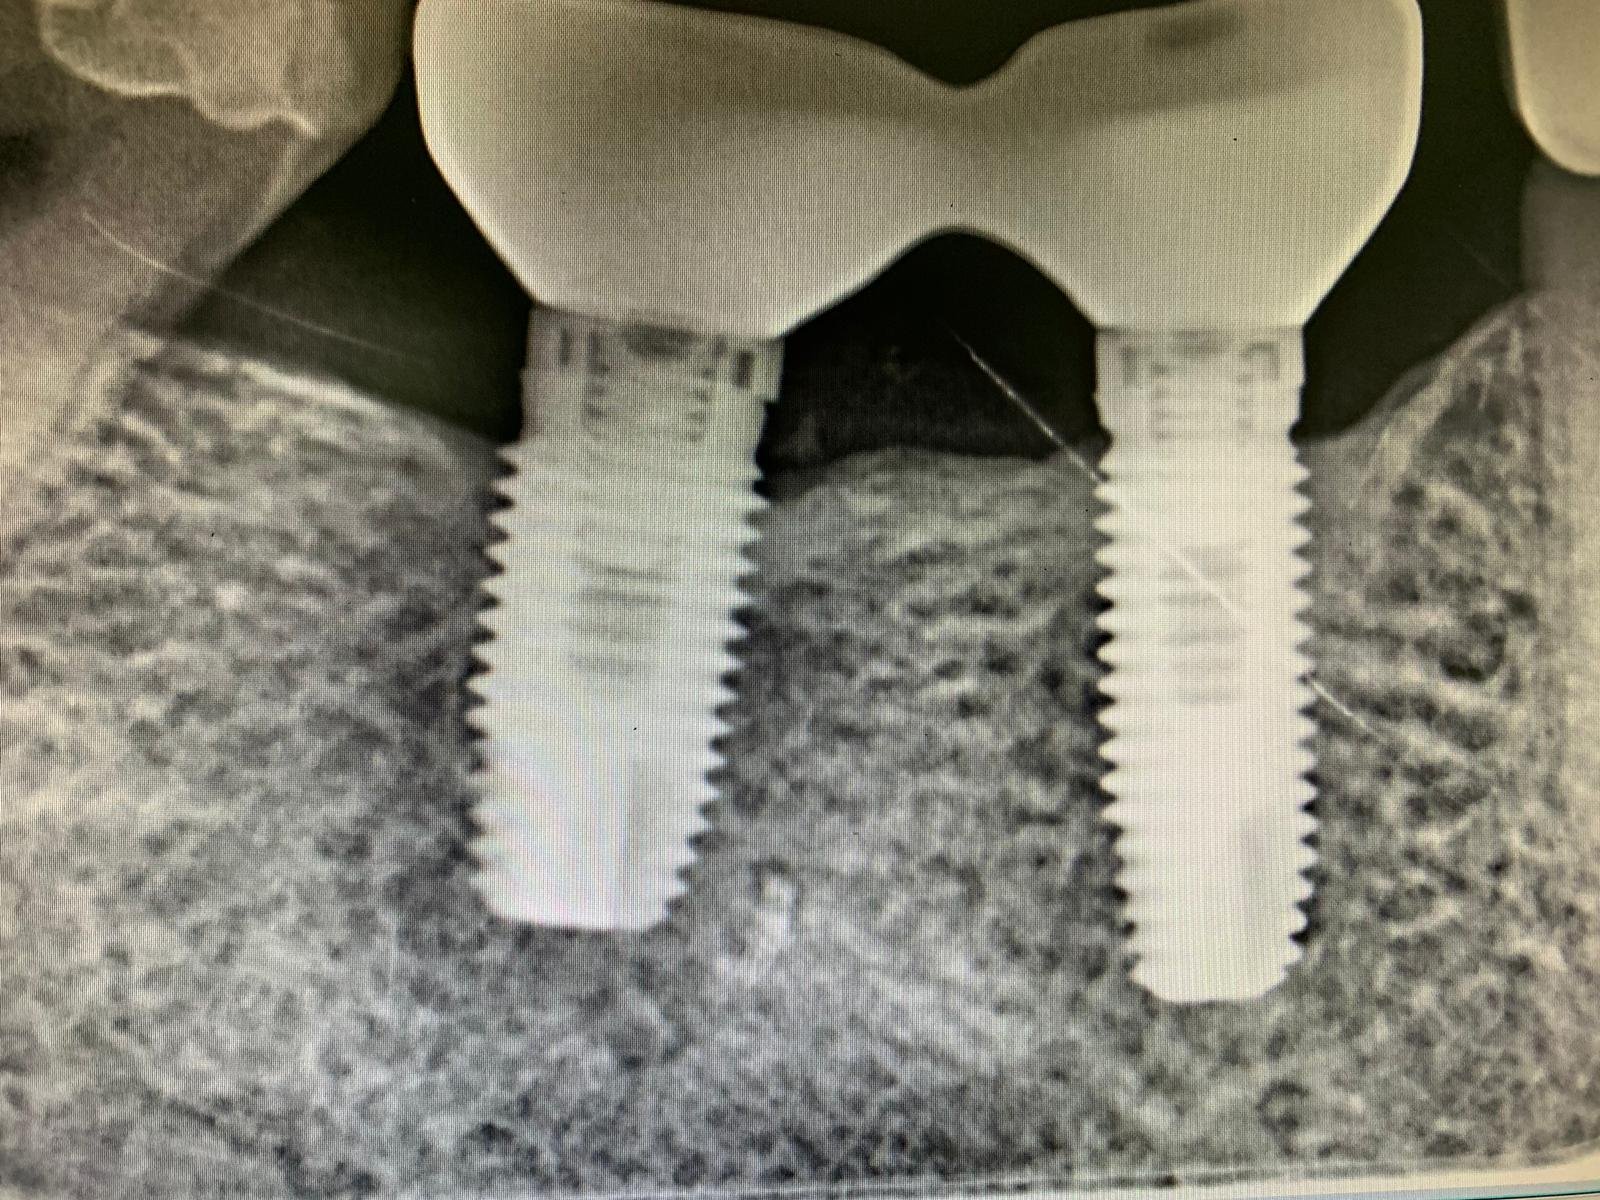

Identificar implantes molares superiores

Paciente acude a consulta con los 4 implantes de los molares colocados , los cuales queremos usar junto a los otros 4 que hemos colocado para realizar una prótesis sobre [...]